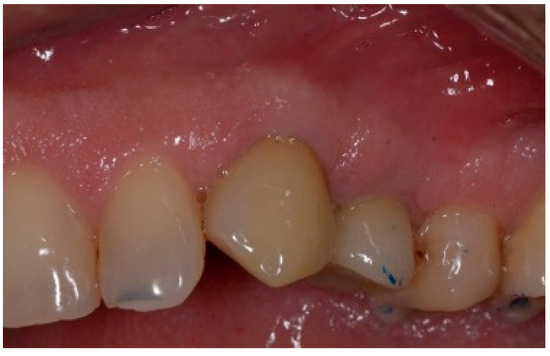

The patient accepted the proposed treatment plan. The preoperative surgical protocol described in patient 1 was followed. An L-shaped aesthetic flap design was chosen to treat this case. The flap started with an incision extending from the distal line angle of the central incisor to the mesial line angle of the canine. A vertical incision was carried out past the mucogingival junction, followed by the elevation of a full-thickness flap. The remaining tooth root was extracted, maintaining the existing facial bone (Figure 9).

Figure 9.

Clinical view of implant replacing.

A 51-year-old male in good health and a non-smoker presented to our clinic with a fractured lateral incisor. Clinical and radiographic examination deemed to tooth non-restorable (Figure 8). The treatment plan proposed was to extract the tooth and place an immediate implant with simultaneous bone regeneration of the buccal wall.

Figure 8.